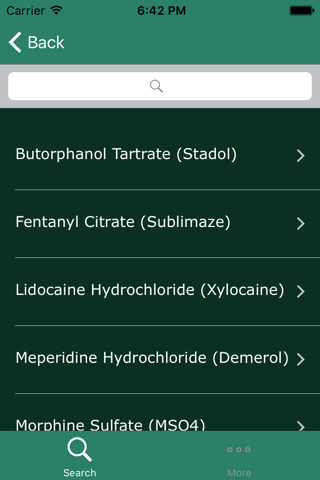

MedRads provides a quick and easy reference for commonly used medications in Radiology. User can perform a keyword search for a particular medication or browse through the broader categories. This application would be particularly helpful for residents and medical students rotating in Radiology.